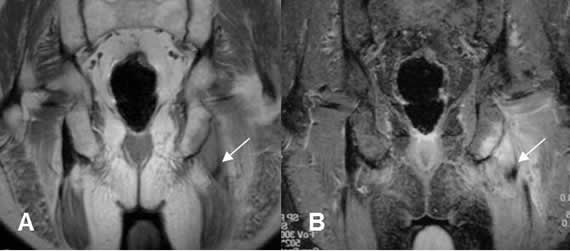

Fig 53. Avulsión.

A: RM coronal en T1 y B: RM coronal en STIR. Cambios inflamatorios sobre la tuberosidad isquiática izquierda por avulsión. Hay retracción en el origen de los isquiotibiales.